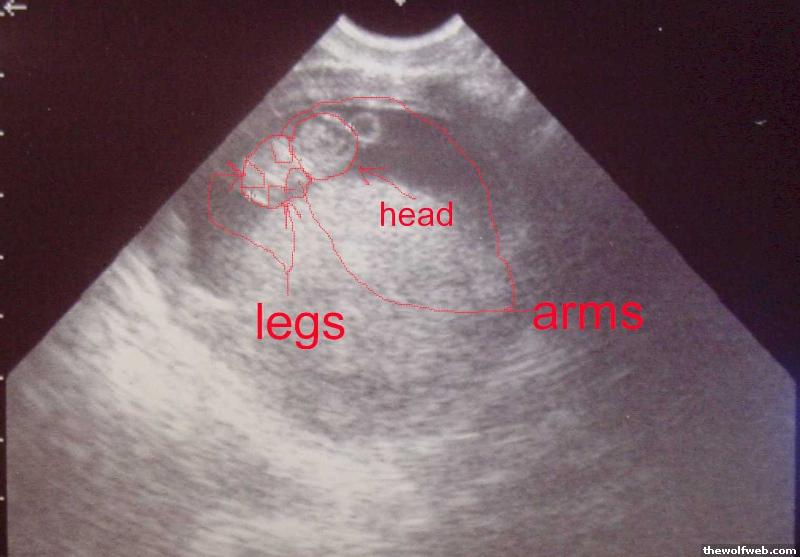

Baby Picture